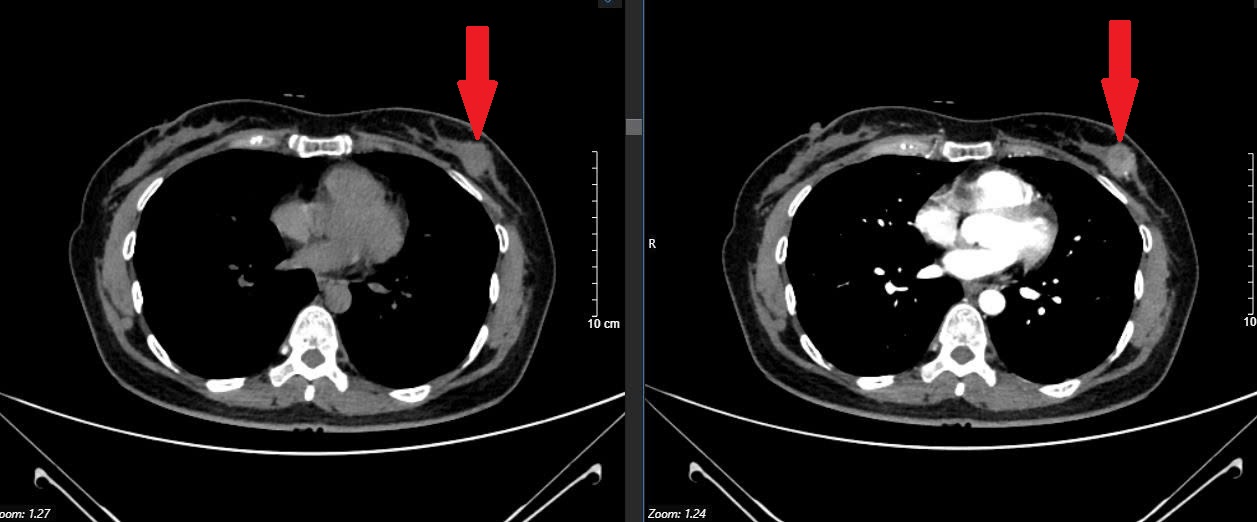

Kết quả siêu âm tuyến vú của chị cho thấy có dấu hiệu bất thường, bác sĩ tiếp tục chỉ định chụp nhũ ảnh (CT nhũ). Kết quả hình ảnh cho thấy tổn thương nghi ngờ ác tính, chị được khuyên nên sinh thiết để xác định chính xác. Lúc nhận thông tin, bệnh nhân thực sự bị sốc, vì không tin nổi mình lại mắc ung thư khi cơ thể vẫn khỏe mạnh bình thường.

Kết quả giải phẫu bệnh sau đó xác nhận ung thư vú giai đoạn sớm. May mắn, khối u chưa di căn và có thể phẫu thuật điều trị khỏi hoàn toàn. Sau phẫu thuật, chị P hồi phục tốt và vẫn duy trì sinh hoạt, làm việc bình thường.